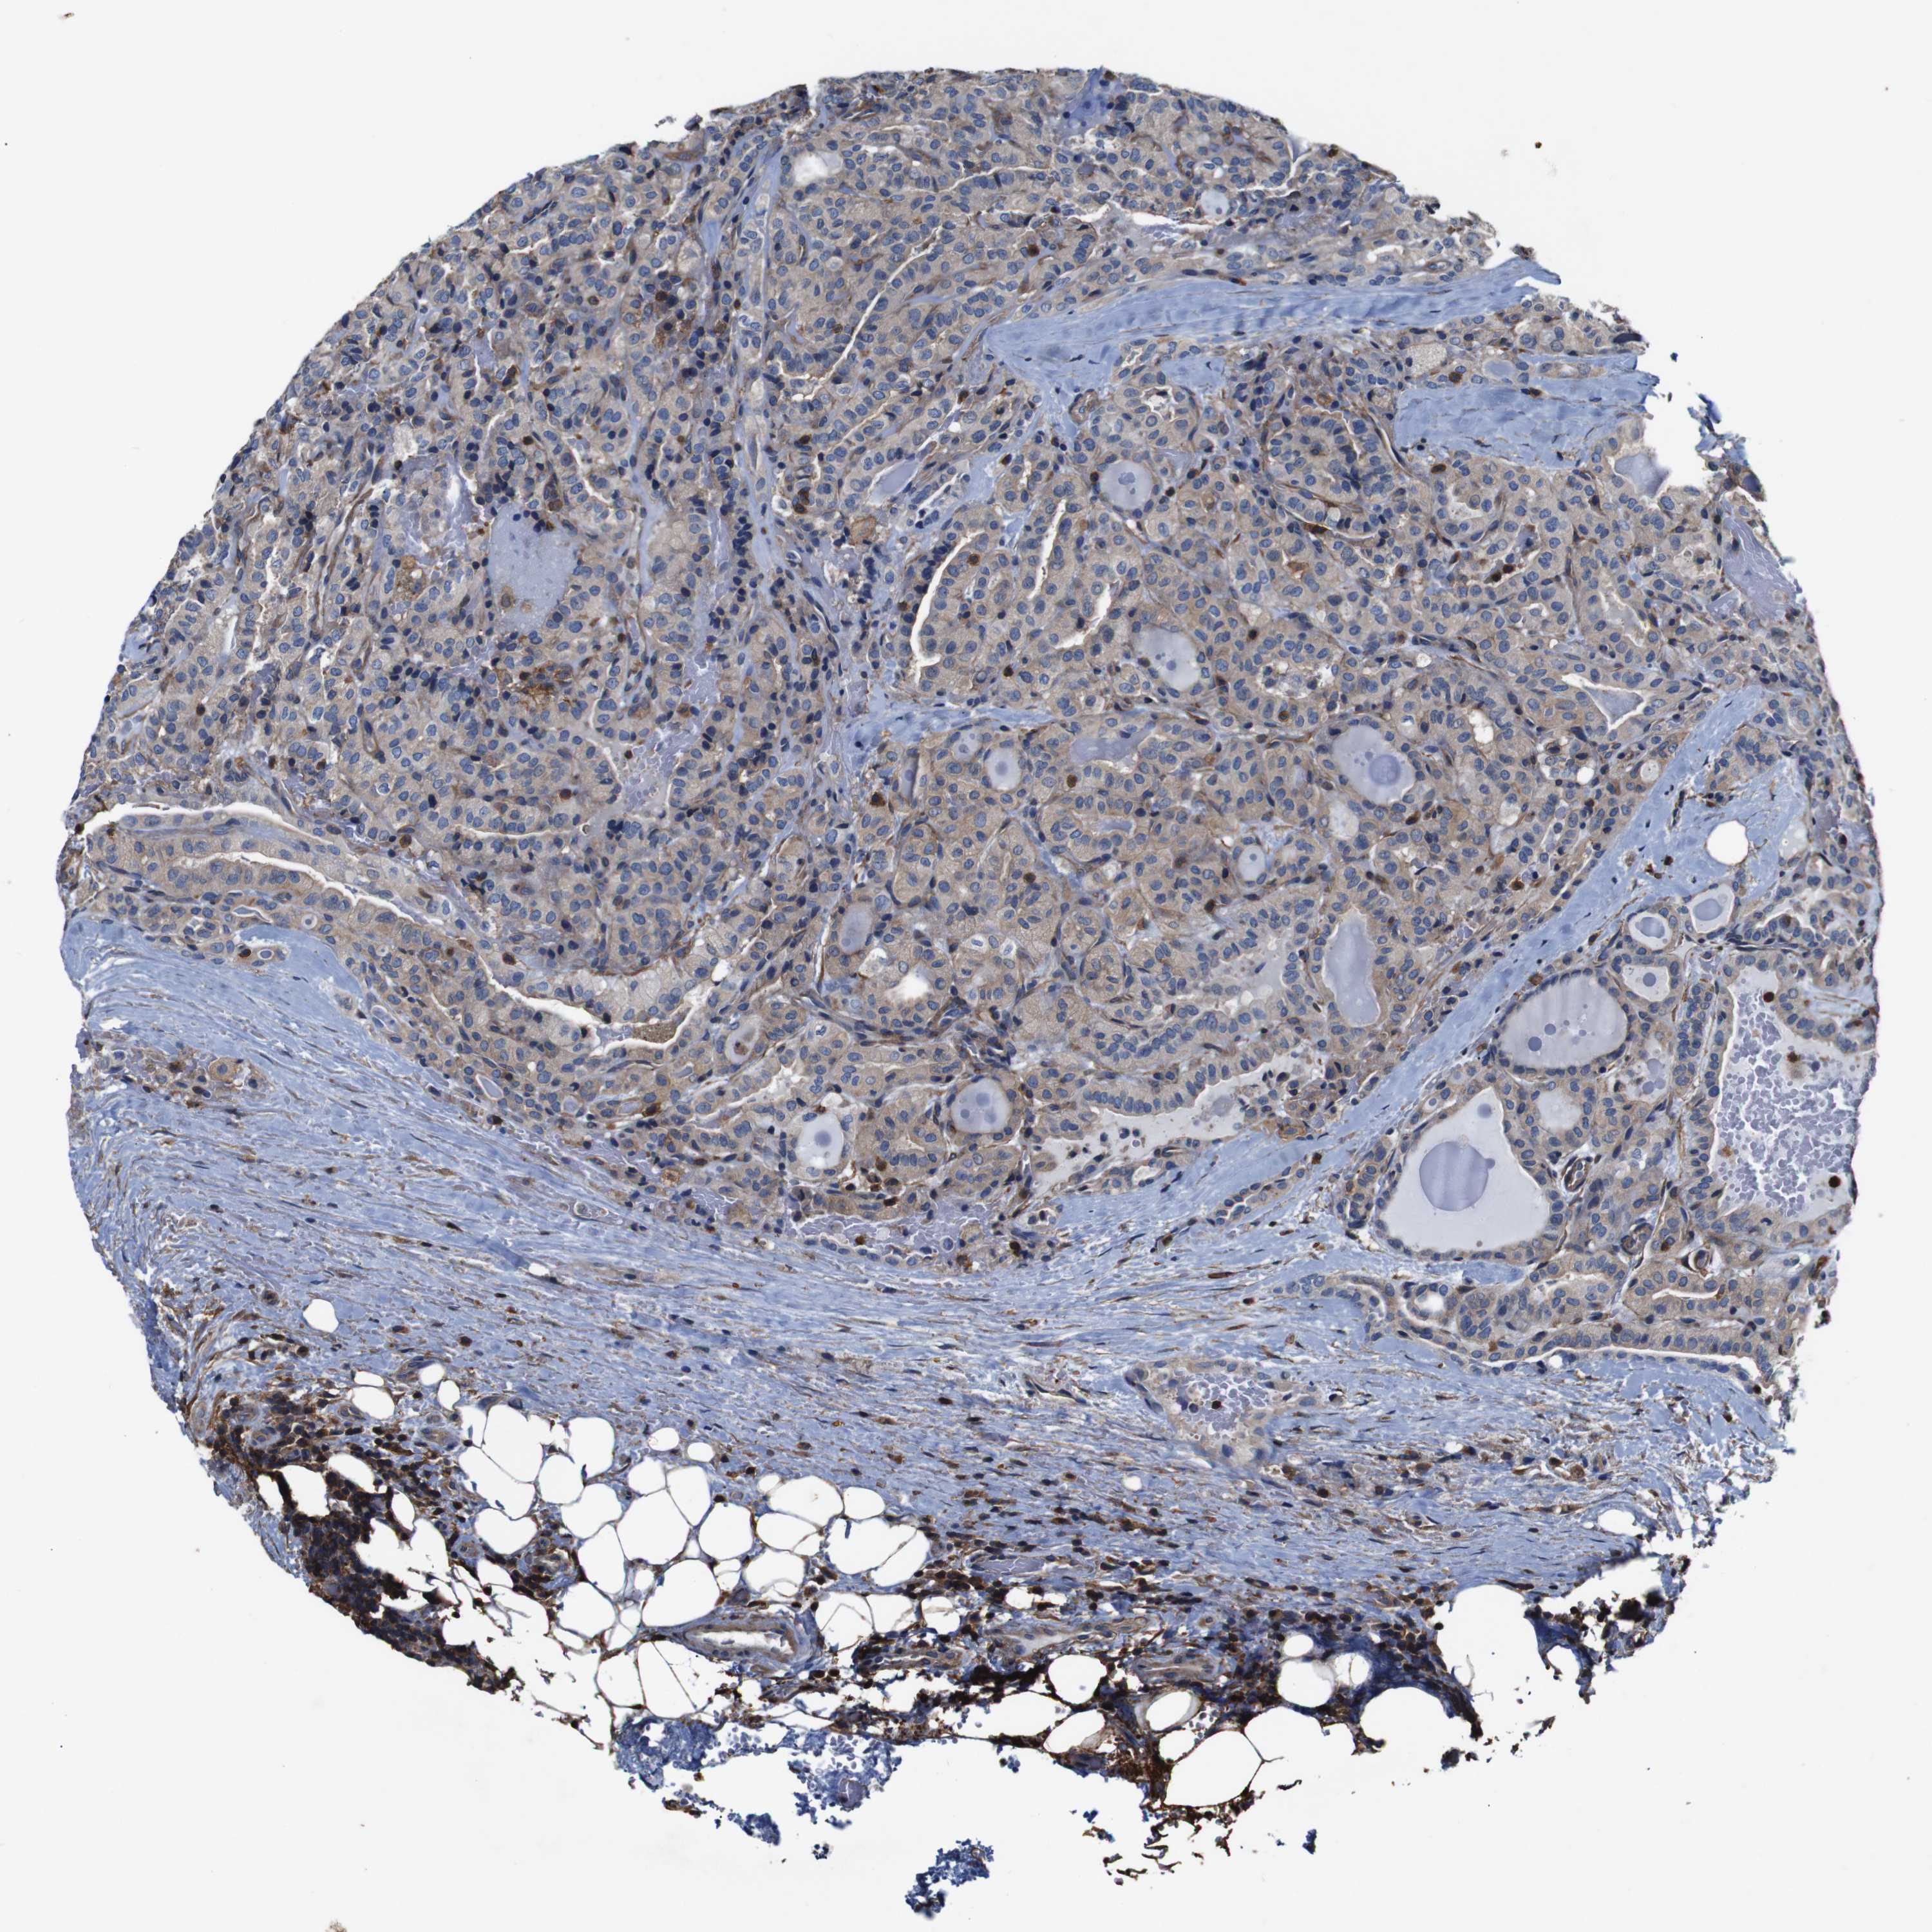

HEAD AND NECK CANCER - Protein expressioni

A mouse-over function shows sample information and annotation data. Click on an image to view it in a full screen mode. Samples can be filtered based on level of antibody staining by selecting one or several of the following categories: high, medium, low and not detected. The assay and annotation is described here.

Antibody stainingi

Antibody staining in the annotated cell types in the current human tissue is reported as not detected, low, medium, or high, based on conventional immunohistochemistry profiling in selected tissues. This score is based on the combination of the staining intensity and fraction of stained cells.

Each image is clickable and will lead to virtual microscopy that enables deeper exploration of all samples and also displays staining intensity scores, fraction scores and subcellular localization as well as patient and tissue information for each sample.

Antibody CAB009092

Staining

High

Medium

Low

Not detected

Intensity

Strong

Moderate

Weak

Negative

Quantity

>75%

75%-25%

<25%

None

Location

Nuclear

Cytoplasmic/membranous

Cytoplasmic/membranous,nuclear

Squamous cell carcinoma, NOS

Squamous cell carcinoma, metastatic, NOS

Adenocarcinoma, NOS